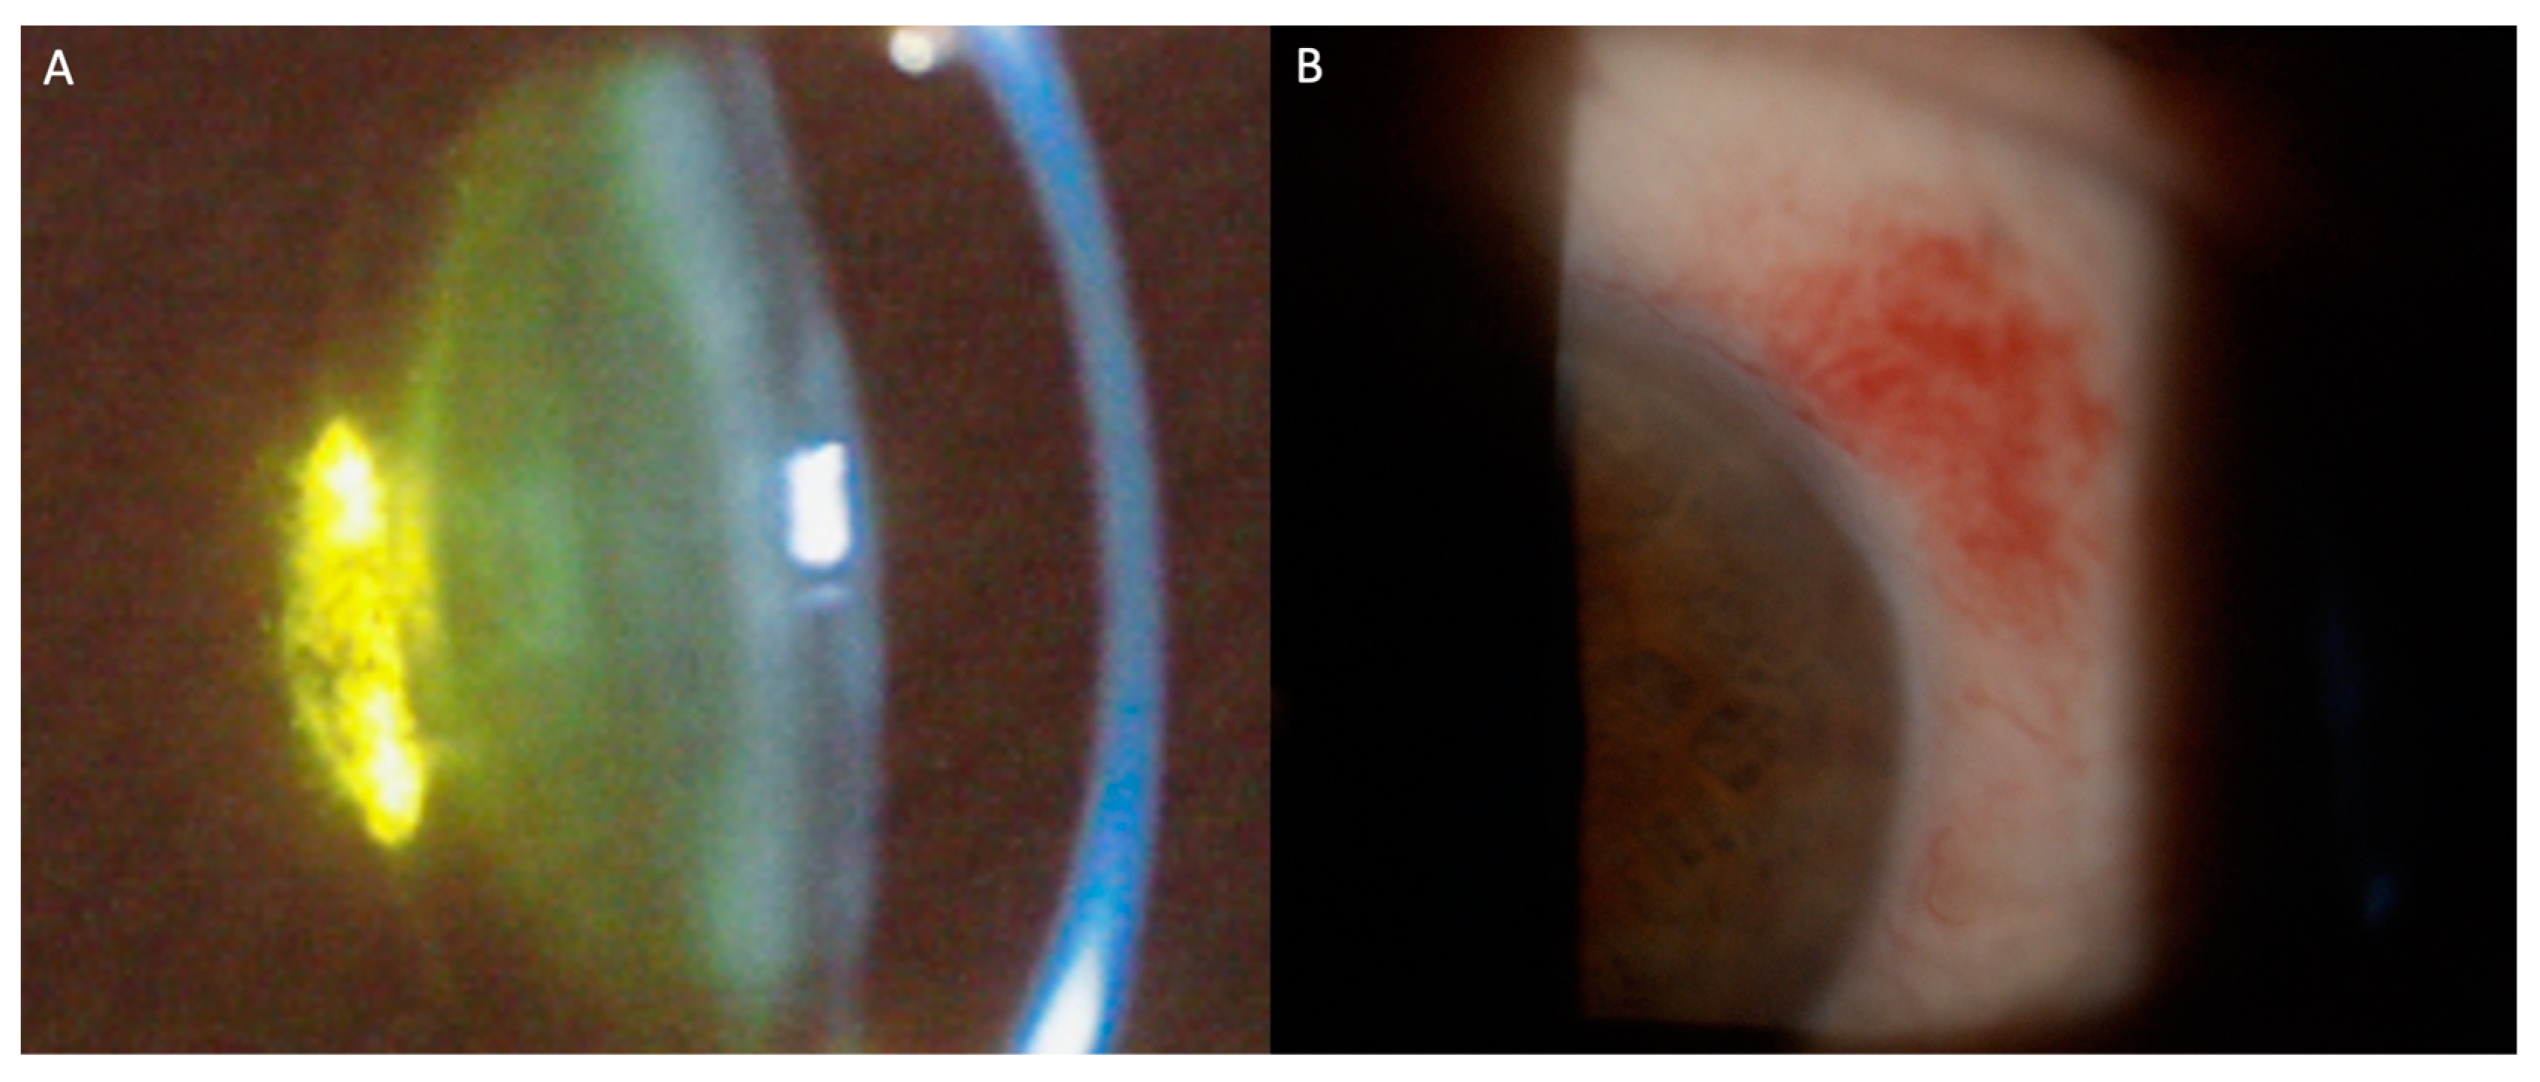

Systemic chemotherapy and targeted therapies used in leukemia treatment may cause significant ocular morbidity. Frequent findings include posterior subcapsular cataracts and subconjunctival hemorrhages (Figure 2A,B). Table 2 represents the most frequent ocular findings in patients treated with systemic agents.

Figure 2. Slit-lamp photographs of signs of ocular toxicities to antineoplastic agents. (A) Posterior subcapsular cataract; (B) Conjunctival hemorrhage.